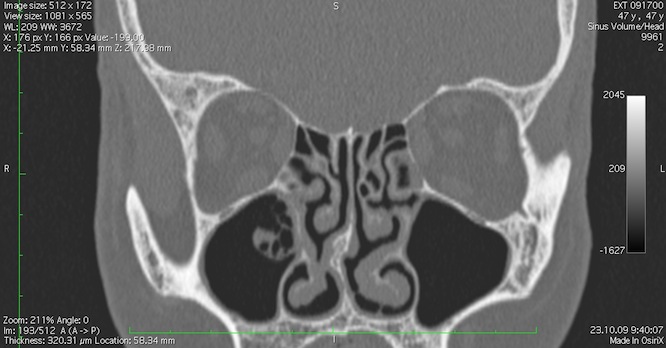

При выполнении компьютерной томографии на экране можно четко увидеть контуры, плотность, форму и структуру внутренней оболочки полостей пазух, слезных протоков, а также наличие минерализации. Это позволяет провести точную оценку размеров, состояния и структуры соустьев пазух носа. В процессе КТ-исследования быстро и безошибочно выявляются осложнения и последствия синуситов, такие как перегородочный (пресептальный) целлюлит, абсцессы краниального и орбитального отделов. Также при проведении КТ-исследования можно обнаружить врожденные или приобретенные нарушения вентиляции полости носа и ее придаточных пазух, такие как искривление перегородок, образование шпор, разрастание, изменения строения соустий и другие.

| Заболевание | Характеристика патологии | Фотография | Описание снимка |

|---|---|---|---|

| Острый синусит | Воспаление околоносовых пазух, протекающее в острой форме с присоединением болей, температуры, отека слизистой | ![]() |

Снижение воздушности за счет большого количества экссудата, возможно наличие четко горизонтальной линии, говорящей о большом количестве жидкости |

| Хронический синусит | Воспаление слизистой оболочки пазух, протекающее длительное время с периодами ремиссии и обострения | ![]() |

Снижение воздушности, увеличение толщины слизистой оболочки |